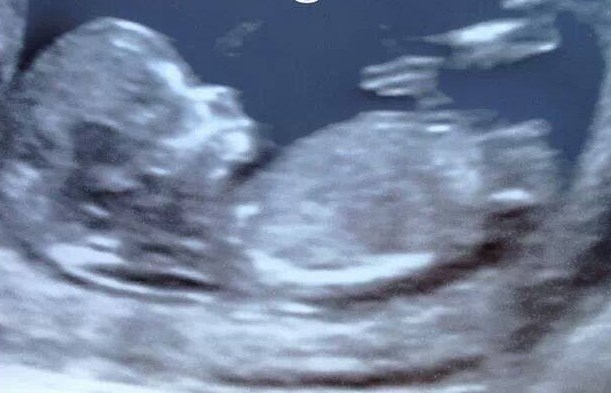

First time posting and hoping I am posting in the right thread but can you have a little look and see what you think about this pic, boy or girl??!!